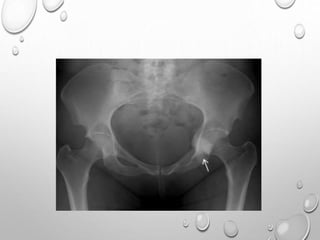

PELVIS : BILATERAL POSTERIOR ILIAC HORNS ORIGINATE FROM

SEPARATE

OSSIFICATION CENTER…..PATHOGNOMONIC

KNEE : HYPOPLASTIC OR ABSENT PATELLA

ASYMMETRIC DEVELOPMENT OF FEMORAL CONDYLES

ELBOW : LATERAL EPICONDYLE OF DISTAL HUMERUS , CAPITULUM ARE

HYPOPLASTIC

….PRODUCING INCREASED CARRYING ANGLE , DISLOCATION OF

RADIAL

HEAD.

HAND : CLINODACTYLY

SHORT 5TH METACARPAL